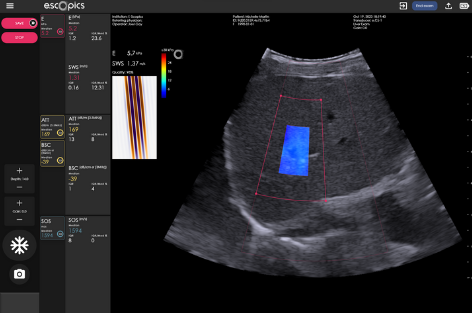

2 modalities: 2DTE & QUS

2DTE

LSM under image guidance

50Hz-transient vibration elastography

Reproducible and repeatable quantitative measurements performed in real time, under image guidance

Hepatoscope 2DTE (two-dimensional transient elastography)is the most advanced ultrasound technology for liver stiffness measurements (LSM), integrating both transient elastography (Catheline, Wu, and Fink 1999) and ultrafast ultrasound (Tanter and Fink 2014) implemented in an ultraportable format.